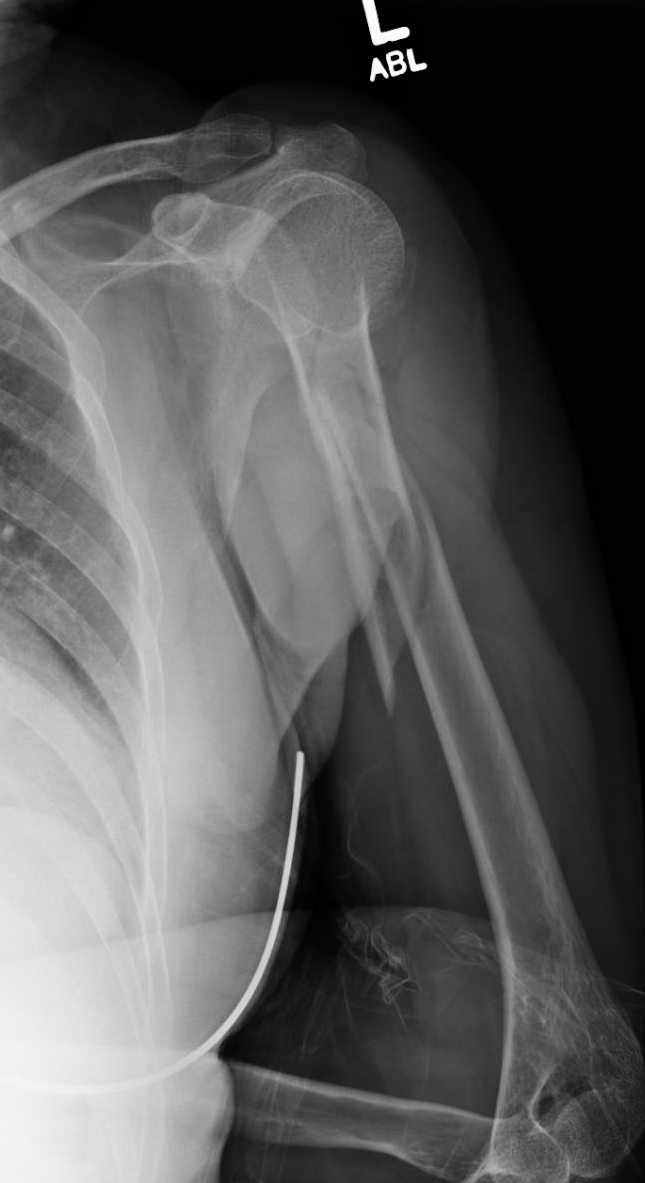

Radial head fracture, proximal radius fracture.

Use an oscillating saw or a rongeur to evenly resect the proximal radius perpendicular to the axis of the radial neck (figure 4). Swelling in the elbow joint. The fracture is more evident on the lateral view. Ebraheim's educational animated video describes the condition of radial head fractures, which are usually caused by falling onto an outstretched. The most common mechanism is a fall onto the outstretched arm with a valgus stress at the elbow. Radial head fractures are a type of elbow fracture. Pain on the outside of the elbow. Radial neck fractures are uncommon and account for 8% of all elbow fractures in children. Part a general considerations, conservative treatment, and open reduction and internal fixation. The head of the radius articulates with the capitulum of the humerus. Diagnosis of radial head elbow fracture is carried out in the following. Depending on the severity of the fracture, surgical procedure may be necessary. There are numerous classification systems that describe fractures of the distal radius, traditionally chosen by the clinician based on preference. Radial head fracture xray / diagnositc tests. 27, 66, 86 radial head fractures occur in about 17% to 19. Surgeries may include partial fragment removal or radial head replacement if the fragmentation is too severe 1. Radial head fracture, proximal radius fracture.